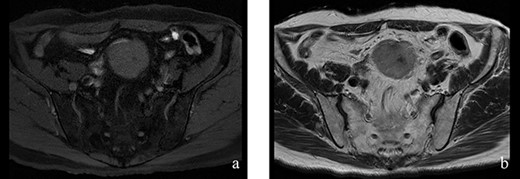

A 70-year-old man underwent robot-assisted laparoscopic cystectomy with bladder replacement for bladder cancer. The pathological diagnosis was stage 0 (Tis, N0, M0). Nine months after the operation, no plain computed tomography (CT) findings indicated cancer recurrence. Thirteen months after the operation, contrast-enhanced CT showed a well-defined intra-abdominal mass, up to 50 × 40 mm in size, with heterogeneous enhancement. The tumor was in contact with the small intestine (Fig. 1). Magnetic resonance imaging (MRI) revealed an isolated mass with hypointensity on T1-weighted images and mild hyperintensity on T2-weighted images (Fig. 2a and b). Fluorine-18 fluorodeoxyglucose positron emission tomography CT (FDG-PET/CT) revealed mild FDG uptake in the tumor, with a maximum standardized uptake value (SUV max) of 3.4 (Fig. 3). Based on these findings, bladder cancer recurrence or mesenchymal tumors derived from the small intestine or mesentery were suspected. The tumor showed a rapid growth trend and required immediate therapeutic intervention. However, a differential diagnosis based on the imaging findings alone was difficult to achieve. Therefore, we decided to perform a diagnostic surgery to identify the intra-abdominal tumor.

Figure 2: (a, b) The tumor had hypointensity on the T1-weighted images and mild hyperintensity on the T2-weighted images.